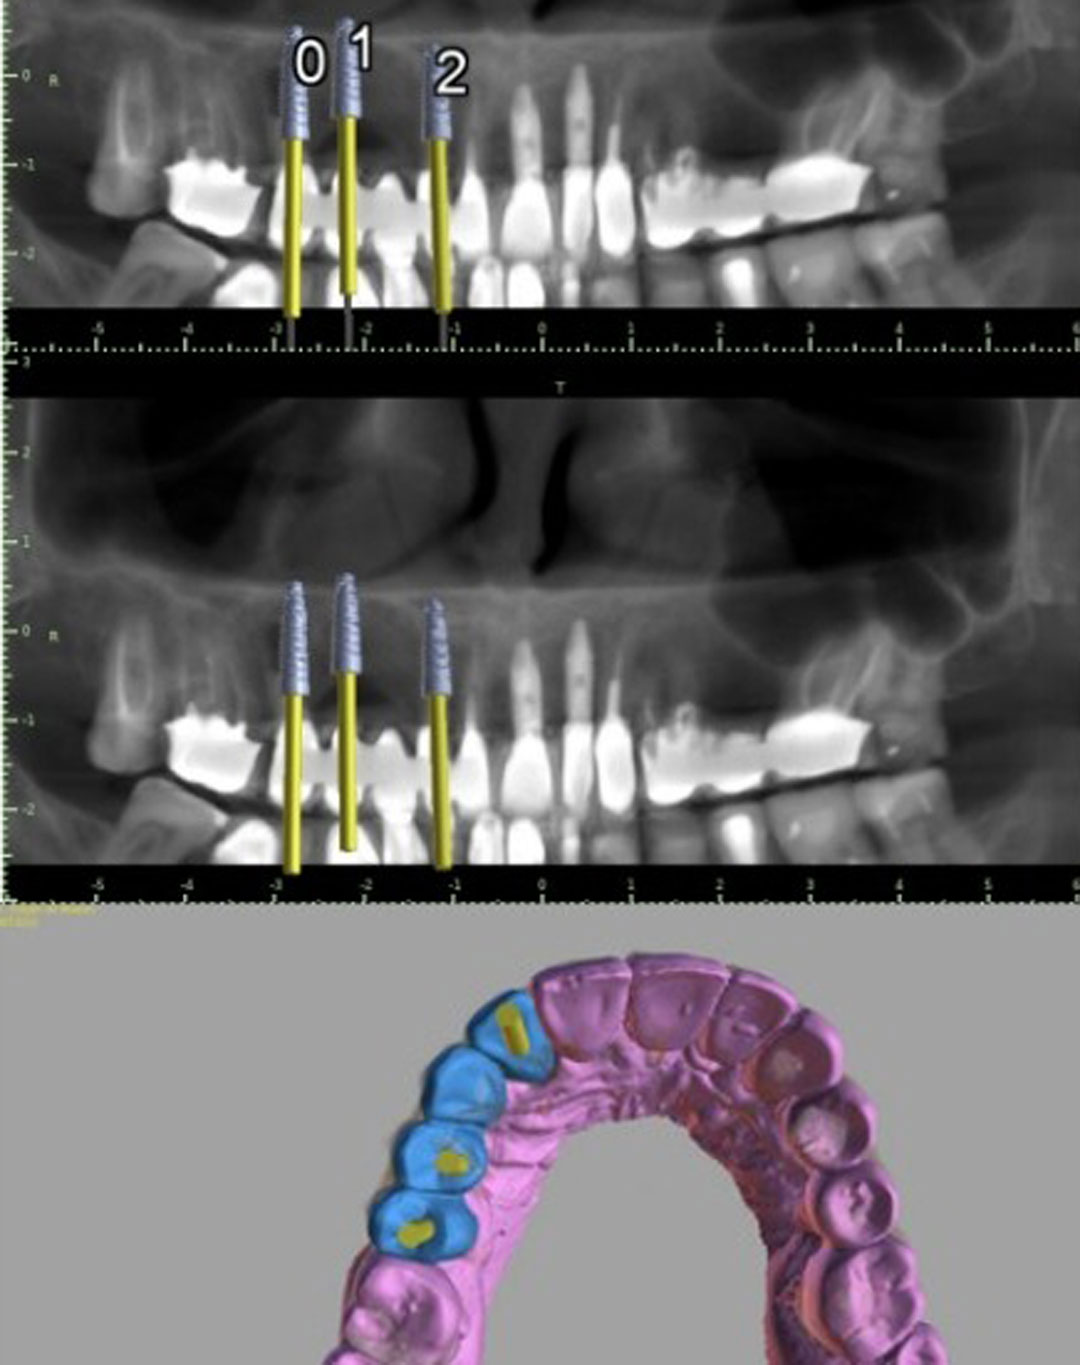

PROPOMOS AS MELHORES SOLUÇÕES PARA AS CIRURGIAS DE IMPLANTES

E MODELOS 3D.